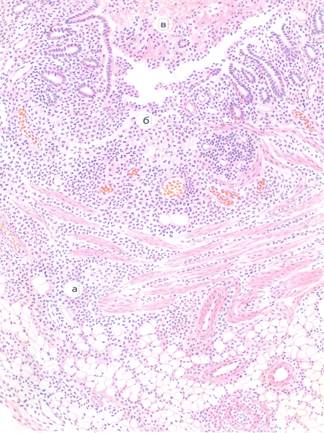

Фолликулярно-язвенный колит. Препарат №183. Окраска гематоксилин эозином. На малом увеличении обнаруживаются язвенные поражения тонкой кишки, пролиферация лимфоидных фолликул. а – некроз; в -